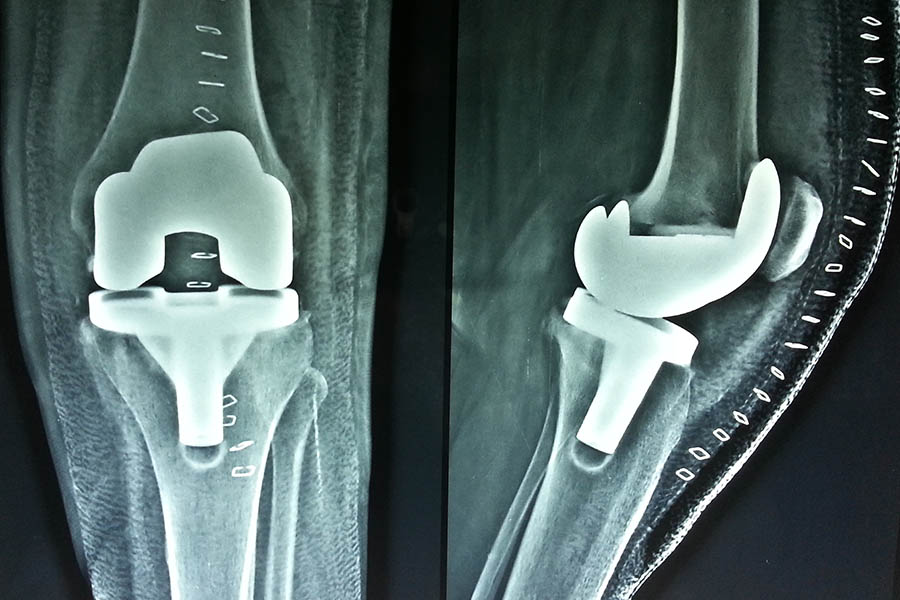

Total Knee Replacement